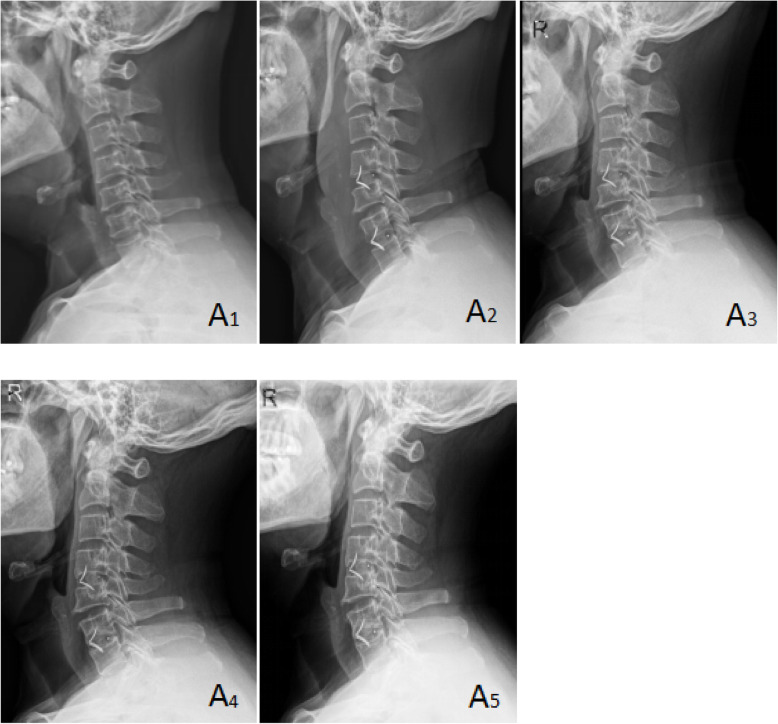

Fig. 1.

A 61-year-old male patient in group A with cervical spondylotic radiculopathy. Preoperative VAS score, JOA score, and NDI score were 7, 12, and 40%, respectively. Postoperative VAS score, JOA score, and NDI score were 1, 17, and 7%, respectively. Postoperative Odom score was “excellent.” Brantigan score: 5 points. A1 was preoperative X-ray plain film of the cervical spine, A2 was immediate X-ray plain film after operation, and A3, A4, and A5 were lateral plain film of the cervical spine at 3, 6, and 12 months after operation, respectively